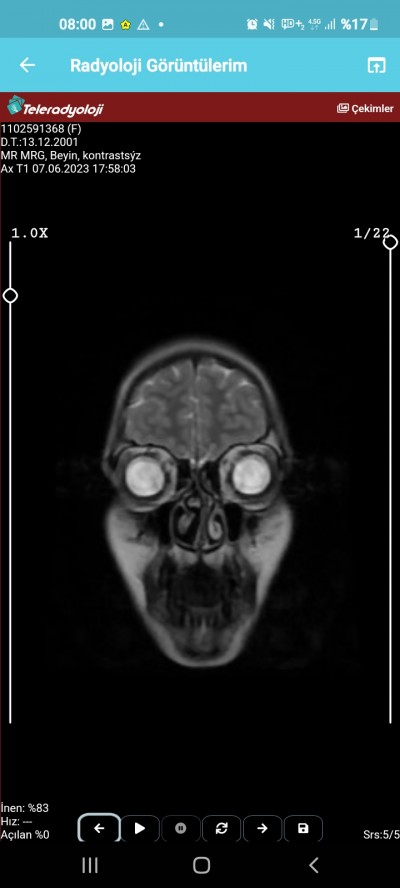

Kızlar sonuçları Çarşamba günü çıkacak başımda inanılmaz bir ağrı var dayanamıyorum artık dün gece çok şiddetlendi dayanamadım.

Lütfen anlayab varsa bakabilir mi bişey var mı

Hayır birşey gözükmüyor cnm eşimin beyninde tümör var böyle görüntü de baya belli sende elhamdülillah birşey yok geçmiş olsun

Mr 100 kusur tane görüntü ile oluşan bir görüntü 3 tane görüntü ile anlamak imkansız ve rapor artı doktorun görmesi lazım rapor cikmis olsa gene biseyler diyebilirdim